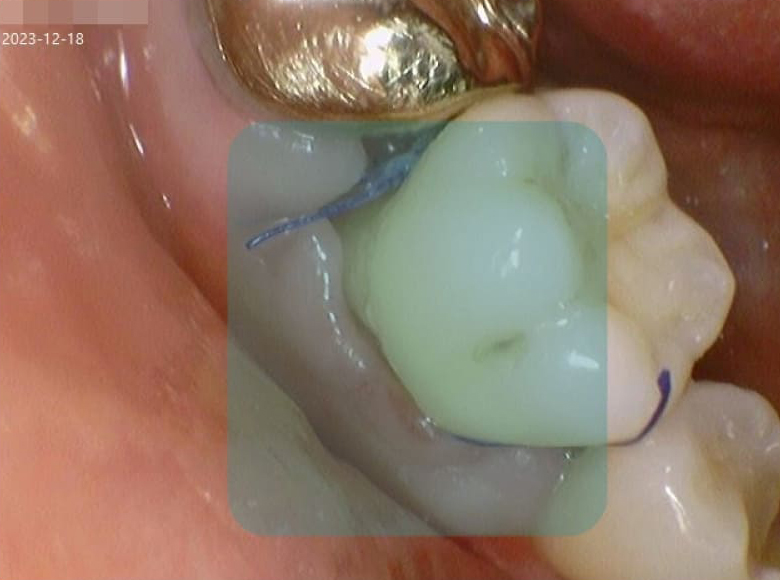

잇몸수술 전후 사진

VS

• Before

중증도의 치주염으로 인해 봉와직염 상태에 이를 정도로 많이 붓고 농이 나오는 상태의 우측 하단의 어금니 부위에 대해 잇몸 수술을 진행했습니다.

• After

잇몸수술 후 2주가 지나 통증과 붓기가 완전히 사라진 것을 확인할 수 있습니다.